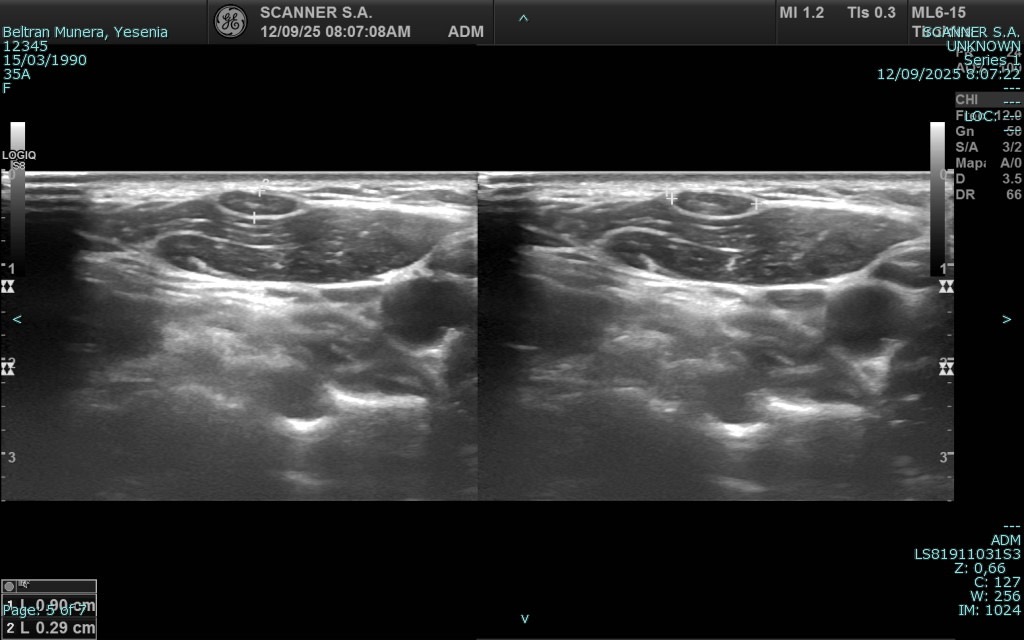

La ecografía es una técnica de diagnóstico por imagen no invasiva que utiliza ondas de ultrasonido para visualizar en tiempo real órganos, tejidos blandos y estructuras internas del cuerpo. A diferencia de otros estudios, no emplea radiación, lo que la convierte en una herramienta segura, ampliamente utilizada en diversas áreas médicas para detectar alteraciones, monitorear enfermedades y apoyar decisiones clínicas con agilidad y precisión.

En SCANNER S.A. contamos con equipos ecográficos de alta resolución, diseñados para ofrecer imágenes claras y detalladas. Nuestro servicio incluye tanto ecografía general como ecografía especializada, permitiendo realizar estudios abdominales, pélvicos, ginecológicos, obstétricos, renales, tiroideos, de partes blandas, musculoesqueléticos y más.